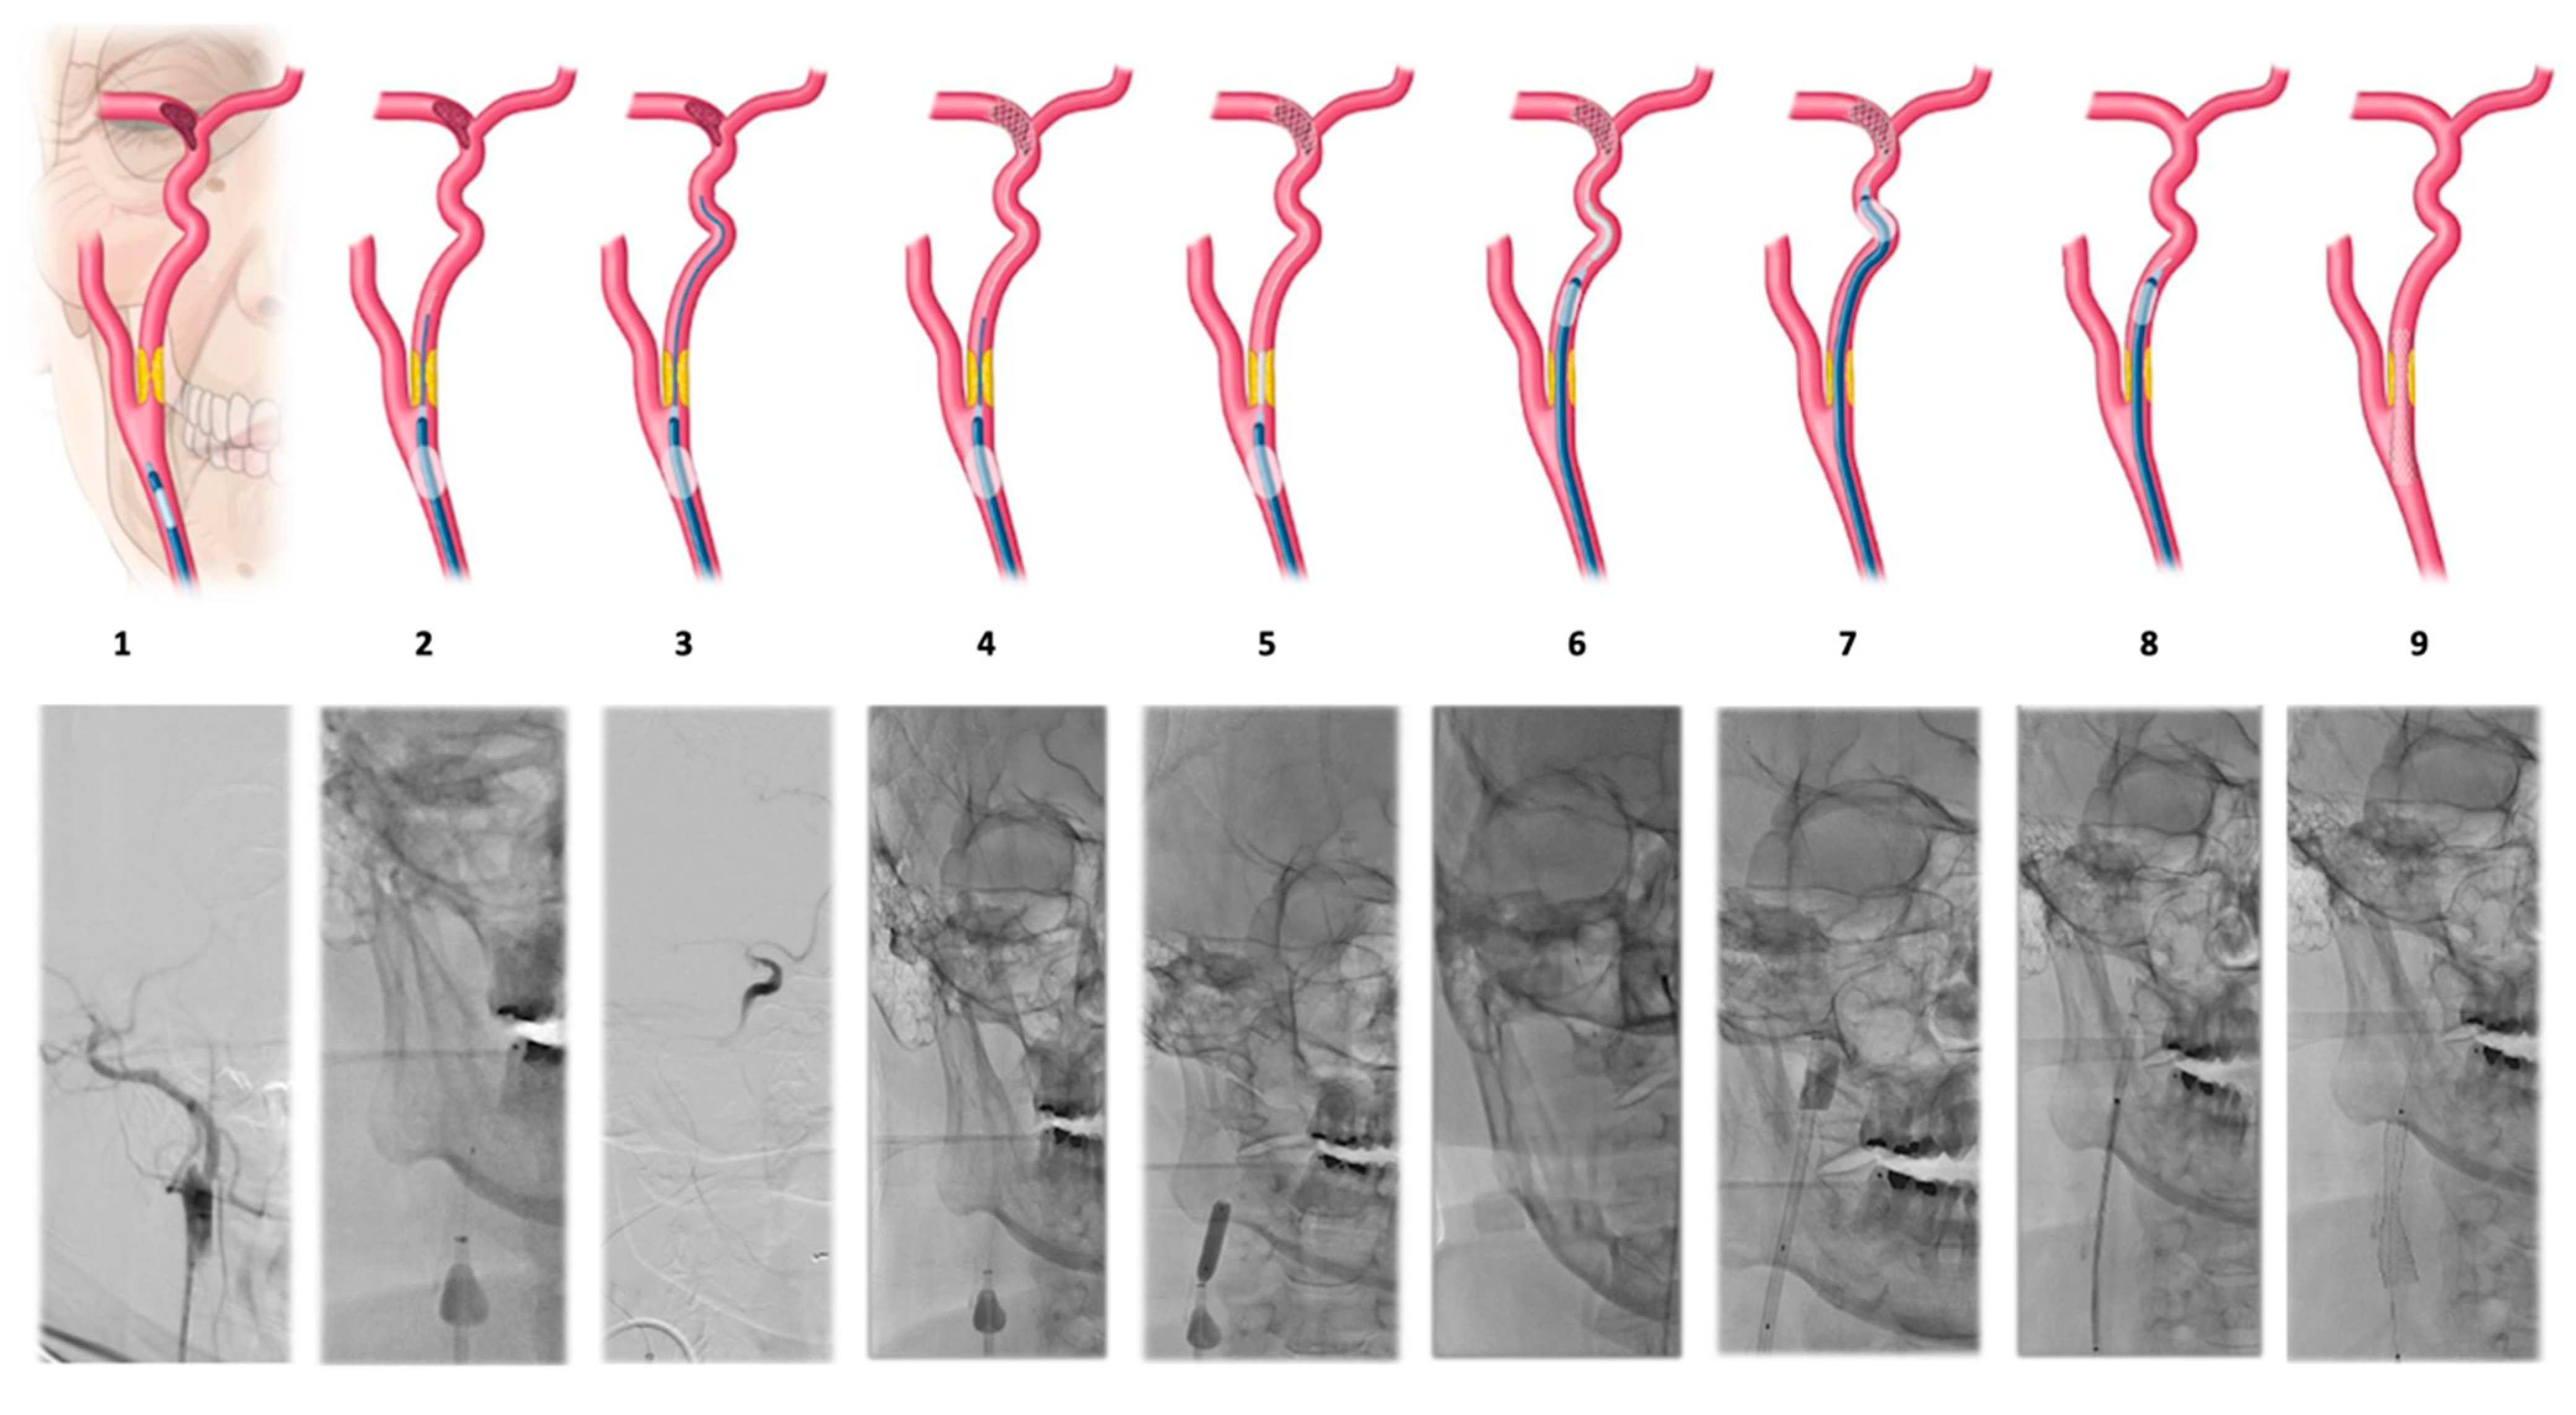

| Step | Description |

|---|---|

| 1 | Common carotid artery (CCA) catheterization with a balloon-guiding catheter (BGC). |

| 2 | Inflation of the balloon in the CCA and cross the atheromatous plaque at the initiation of the internal carotid artery (ICA) with a microcatheter and the micro guidewire. |

| 3 | Make a run through the microcatheter to confirm the presence of thrombi in the ICA and assess thrombi in intracranial arteries. |

| 4 | Deployment of a stent retriever at MCA and distal ICA. |

| 5 | Remove the microcatheter and advancement of the angioplasty balloon using the stent retriever pusher and dilation of the proximal atheromatous plaque. |

| 6 | Deflate the BGC balloon; continuous aspiration through the same catheter with a 60cc syringe. Advance the BGC towards the subpetrosal ICA with the support of the angioplasty balloon. |

| 7 | BCG is inflated again to make a thrombectomy pass with the stent retriever used as distal filter. |

| 8 | Distal to the atheromatous plaque through the BGC and with a 0.014 guidewire, (Traxcess, MicroVention Inc., Tustin, CA, USA) raise the carotid stent. |

| 9 | The carotid stent is implanted to maintain plaque opening. |